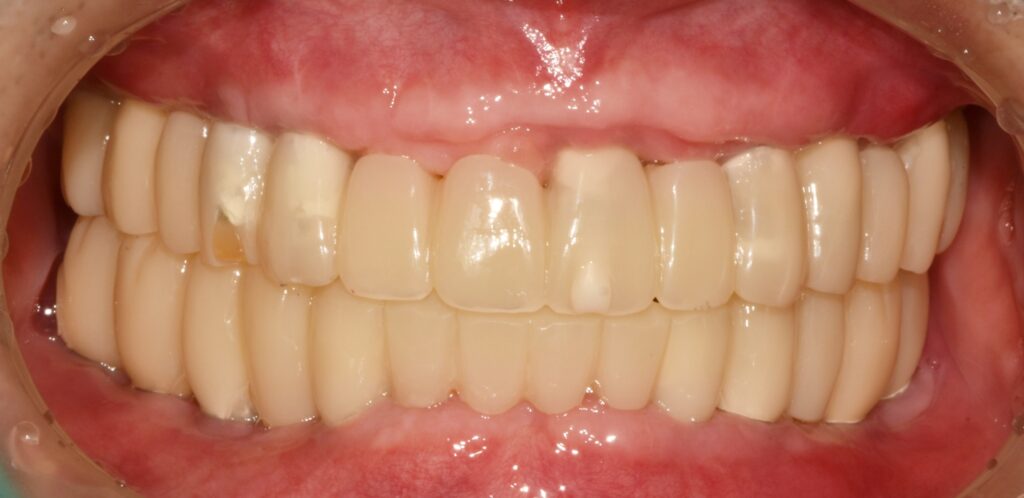

바로 최종 보철로 이행하지 않고 임시치아 기간을 가졌어요.

새로운 치아를 가지게 되었으니 턱관절도 그에 적응해야 하고 씹는 게 불편하지는 않은지 잘 씹히는지, 음식물이 끼지는 않는지

그러한 것들을 지속적으로 확인하면서 필요하면 조절을 해주는 과정입니다.

최종 보철물로 이행

임시 치아 기간을 대략 한 달에서 두 달 정도 갖고 모든 것이 다 좋다고 판단될 때 인상채득을 해서(본을 떠서) 최종 보철물로 이행을 해줍니다.

조화롭게 치료가 잘 된 모습입니다. 당연히 식사도 편하게 잘하시고 그 덕분에 생활에 활력이 넘치고 일이 잘 풀린다고 하셨습니다.

새 삶을 얻으신 것 같다고 후기 남겨주셨어요.^^